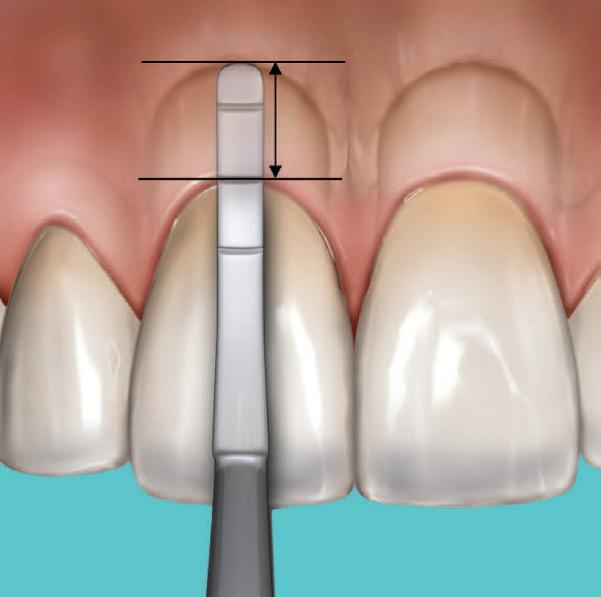

BioHorizons has introduced a new implant system that combines the advanced thread design of the Tapered Pro with the precision and stability of the Conelog conical connection. This integration delivers enhanced surgical handling, improved primary stability, and long-term biological benefits, supporting better patient outcomes in both aesthetic and functional zones.

This case was performed by Dr Homa Zadeh, DDS, PhD, a respected leader in periodontology and implant dentistry. Dr Zadeh’s approach emphasizes biologically driven protocols and evidence-based techniques, making this case a strong example of clinical excellence using the Tapered Pro Conical system. It involves the replacement of two front anterior teeth after they fractured off and the full restoration process.

Fig 1. Patient anterior situation. Two anterior crowns fractured off.

Fig 2. Intraoral radiograph indicating tooth structural loss extent.

Fig 3. Provisional restorations on central incisors and gingival images. The gingival contours were optimal, and the gingival phenotype was thick.

Fig 4. Alveolar bone imaging. The alveolar bone was intact, and the alveolar crest was approximately 4mm apical to the restorative margin.